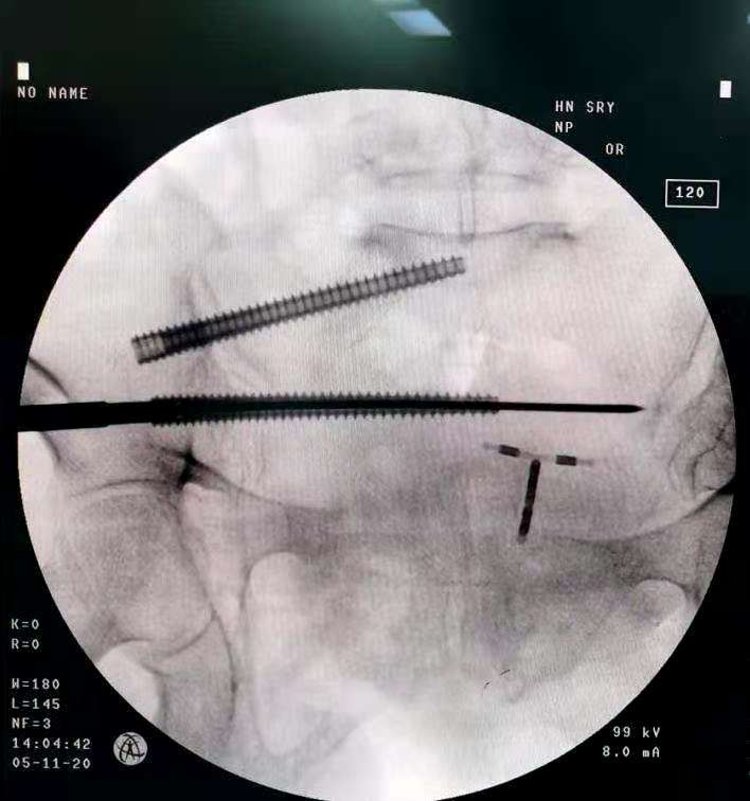

术中,骨科机器人机械臂完美解决了传统骨科手术“看不见、打不准、拿不稳”三大难题,让骨科手术更快更完美。本次手术耗时约30分钟。刘涛主任通过精准定位及机器人机械臂精确运动,规划螺钉方向及长度,避开髋臼关节面及盆腔内重要脏器、大血管,复位骶髂关节后,准确地将两枚长度85毫米的空心螺钉置入骶髂关节,然后又利用机器人导航,成功快速固定了其他骨折部位,顺利完成骨盆骨折微创内固定手术。

不仅如此,为了确保置钉位置的准确,病人还需要反复C臂透视查看置钉位置,X线暴露次数较多,也会对患者身体造成一定损害。